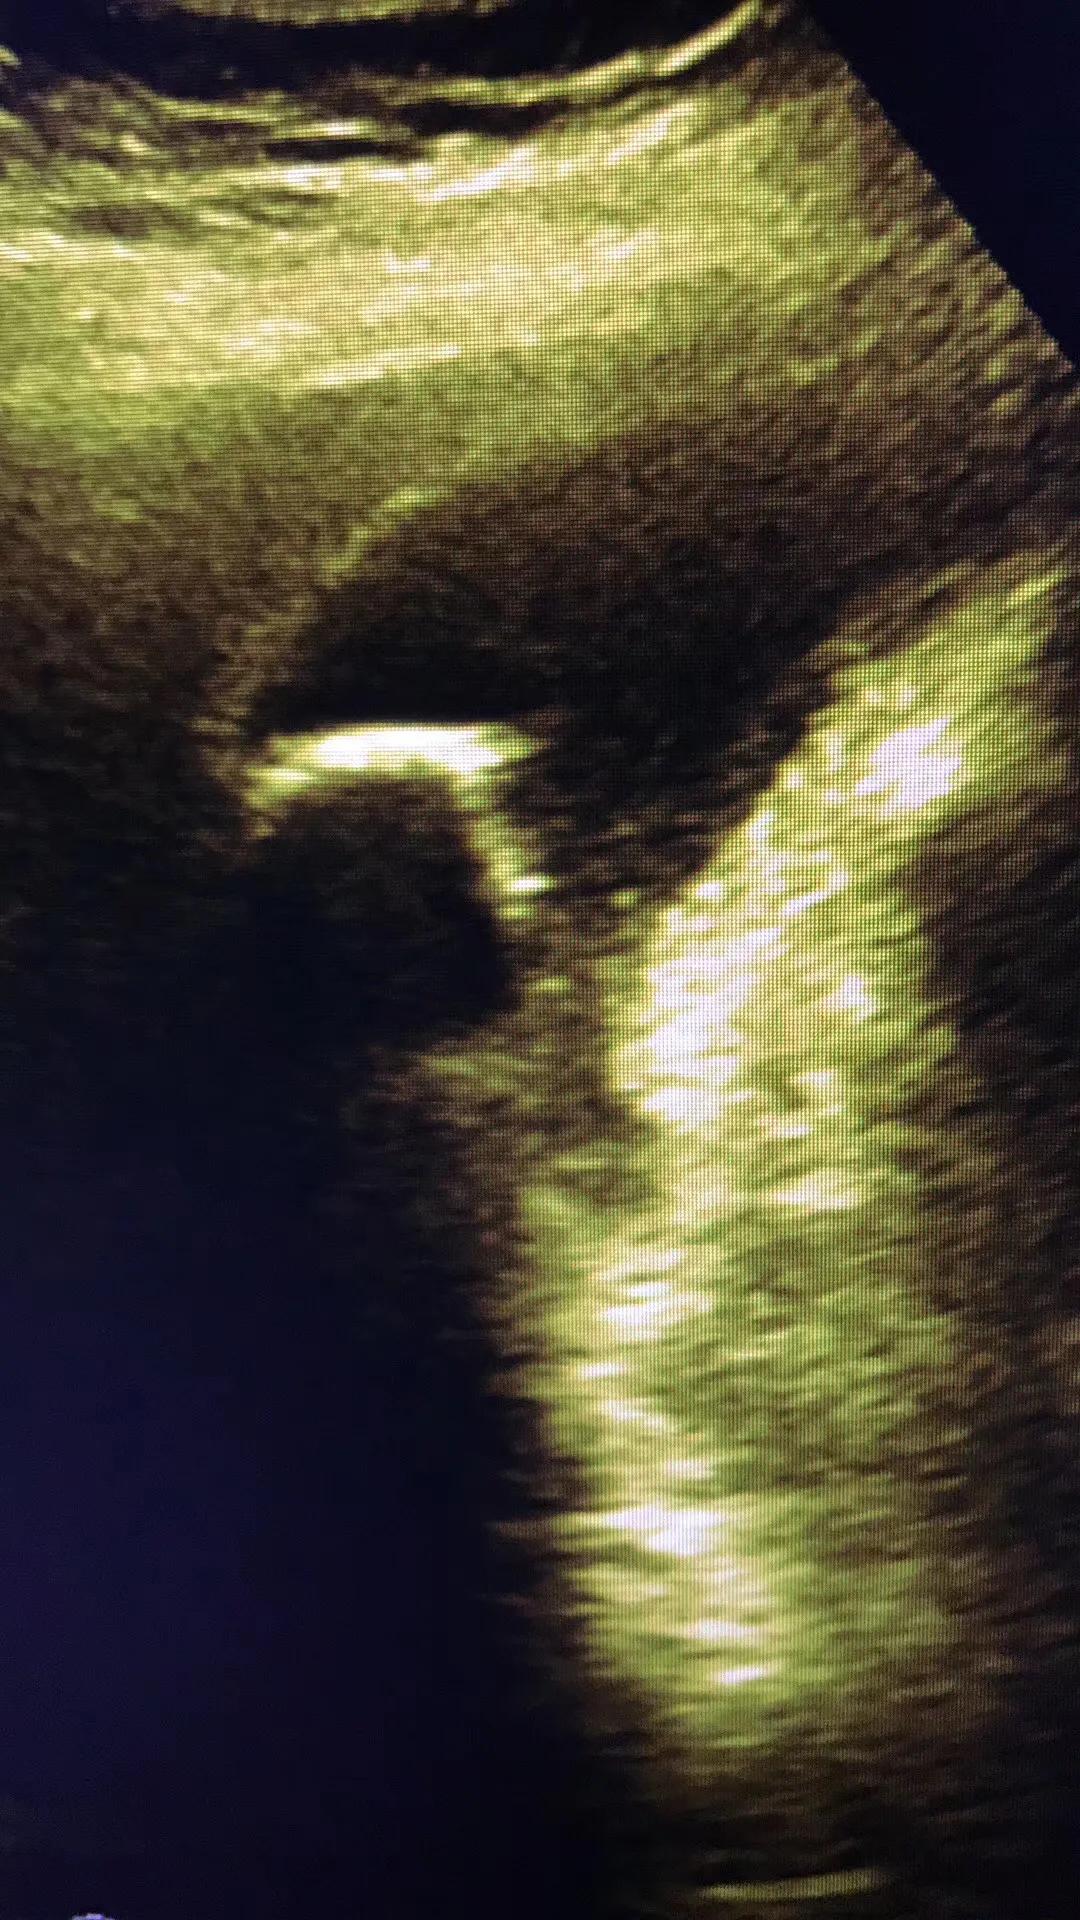

病例1.患者女性,57岁,胆囊颈部结石嵌顿继发急性胆囊炎!胆囊肿的像个茄子!